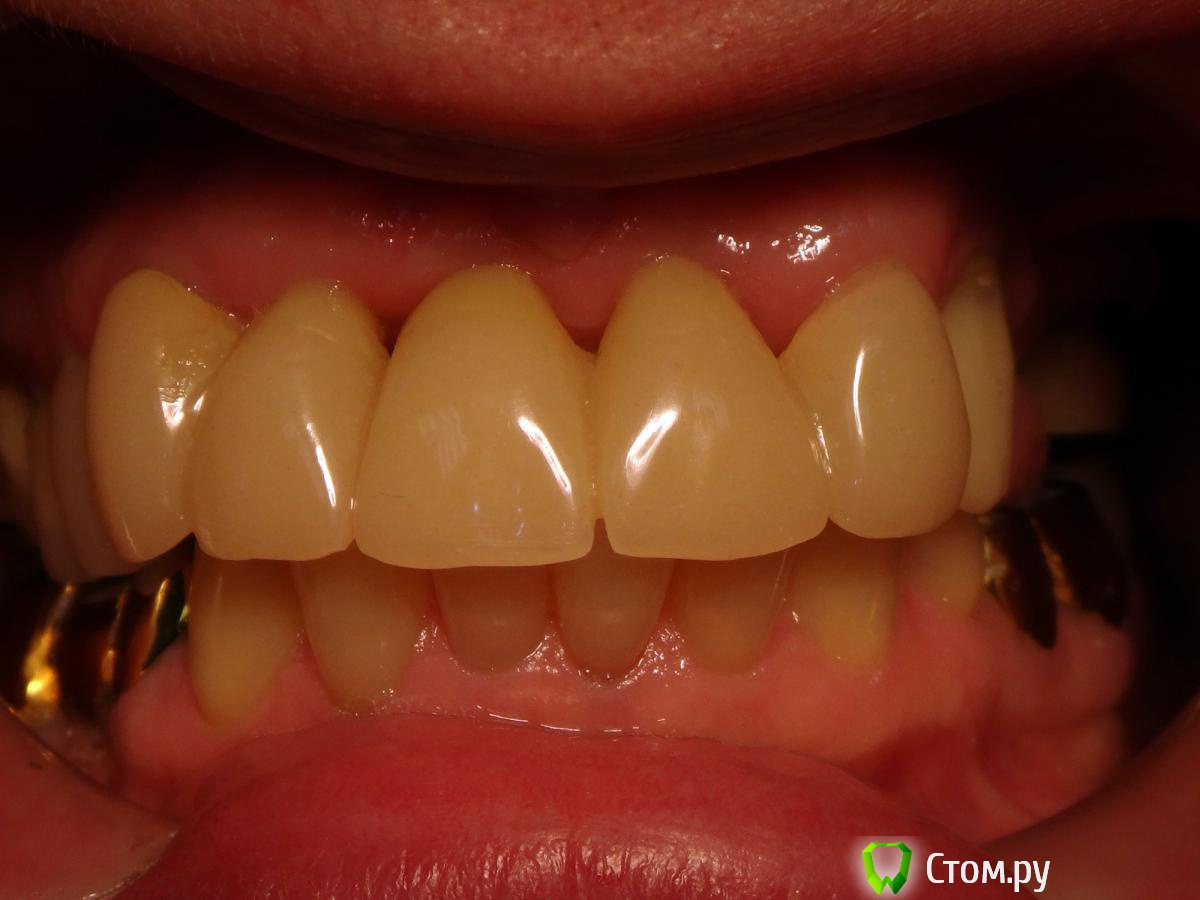

Kalipso Опубликовано 28 августа, 2014 Поделиться Опубликовано 28 августа, 2014 Я ставлю сразу после удаления .1 . Снимаю слепок до удаления , и прошу техника либо сделать коронку или wax up после чего по ключу сама изготавливаю .2. Удаляю .3.Жидкотекучим креплю коронку . Как- то так . Это наверно самая моя первая такая работа .http://s017.radikal.ru/i432/1408/7c/d61e22c1c7ae.jpg http://s018.radikal.ru/i519/1408/d2/23c0aebcd1b4.jpg http://s016.radikal.ru/i336/1408/51/3ede7c77a5d0.jpg http://s41.radikal.ru/i091/1408/cc/604419754cb7.jpg 3 Ссылка на комментарий

Slaggy Опубликовано 11 сентября, 2014 Поделиться Опубликовано 11 сентября, 2014 (изменено) Если планируется удаление переднего зуба, то стараемся одномоментно установить имплантат. Если это невозможно или нельзя нагружать винт, то делаем адгезивный "мериленд". Если пролёт в несколько зубов, то только съёмное. Можно дополню?Если пролет в несколько зубов, но ограничивающие деффект зубы будут обтачиваться, то можно армировать времянки металлом.вторую фотку перезагружаю:Это как раз на 3-4 день овоиды сделаны. первая фотка на 3-4 день после 3-4 дня после удаления.Что скажите мне изменится в поверхностных слоях сгустка и окружающих их тканей за 3-7 дней? Прорастет чем? или что?Нифига не вижу разницы одномоментно или на 3 день. Ааа. Есть разница. Не кровит и можно работать.А еще пациент осознав потерю значимей оценит обретение. Если удаляемый зуб имеет коронку, то можно его использовать для времянки.Извините за качество, не успел отфоткать - фотик сдох, успел пару раз нажать на затвор без подготовки.Вся центральная группа с клиновидными деффектами и подвижна, 21 - выдвинут на 3,5 мм. пациент не хочет с ним расстоваться, держит губами, оберегает.Нужен был быстрый "ход конем", чтоб он на шею не сел. Я пообещал за час сделать лучше чем есть. Пальцами удалил 21, обрезал под овоид, ретроградно запломбировал жидкотекучим, им же залил клиновидный и приклеил, армировав стекловолоконной лентой.Говенная работа, но она позволит мне дальше человека вывести на нормальное лечение.Вообще данный товрисч очень тяжелый, там все под бульдозер, а потом...Еще рас сорри за жесть, но это жизнь, работа, будни ))))) Изменено 11 сентября, 2014 пользователем Slaggy Ссылка на комментарий